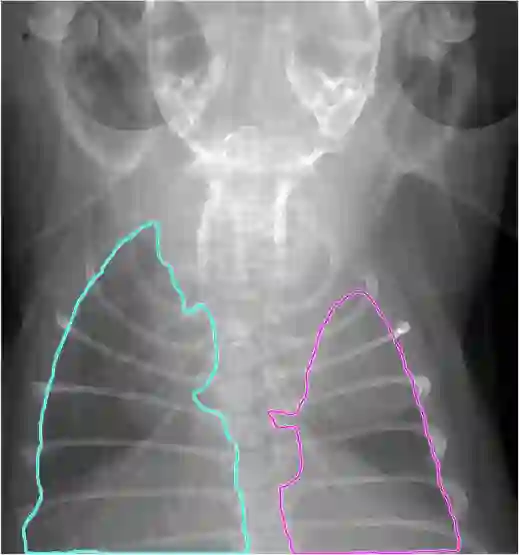

Low-dose computed tomography (LDCT) is the current standard for lung cancer screening, yet its adoption and accessibility remain limited. Many regions lack LDCT infrastructure, and even among those screened, early-stage cancer detection often yield false positives, as shown in the National Lung Screening Trial (NLST) with a sensitivity of 93.8 percent and a false-positive rate of 26.6 percent. We aim to investigate whether X-ray dark-field imaging (DFI) radiograph, a technique sensitive to small-angle scatter from alveolar microstructure and less susceptible to organ shadowing, can significantly improve early-stage lung tumor detection when coupled with deep-learning segmentation. Using paired attenuation (ATTN) and DFI radiograph images of euthanized mouse lungs, we generated realistic synthetic tumors with irregular boundaries and intensity profiles consistent with physical lung contrast. A U-Net segmentation network was trained on small patches using either ATTN, DFI, or a combination of ATTN and DFI channels.Results show that the DFI-only model achieved a true-positive detection rate of 83.7 percent, compared with 51 percent for ATTN-only, while maintaining comparable specificity (90.5 versus 92.9 percent). The combined ATTN and DFI input achieved 79.6 percent sensitivity and 97.6 percent specificity. In conclusion, DFI substantially improves early-tumor detectability in comparison to standard attenuation radiography and shows potential as an accessible, low-cost, low-dose alternative for pre-clinical or limited-resource screening where LDCT is unavailable.